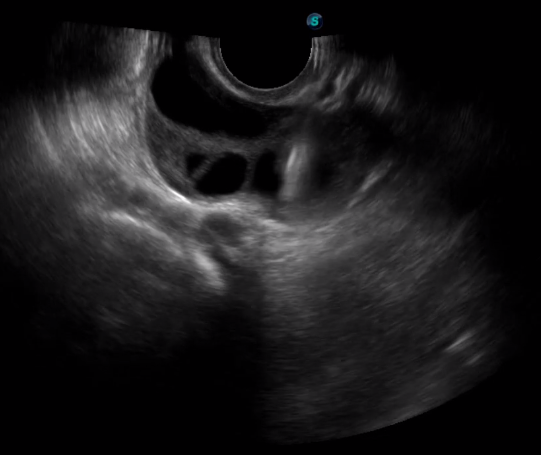

傳統(tǒng)腔內(nèi)探頭采用直柄設(shè)計(jì),在搭配穿刺架使用時(shí),手術(shù)空間小,不易操作;生殖專用的曲柄探頭,探頭柄采用彎曲成角度設(shè)計(jì),可實(shí)現(xiàn)監(jiān)視、取卵兩不誤,搭載穿刺架時(shí),可以清晰顯示穿刺針的進(jìn)針過程、深度和位置,實(shí)時(shí)監(jiān)視取卵全過程,保障取卵操作精準(zhǔn)與安全。

取卵臨床圖